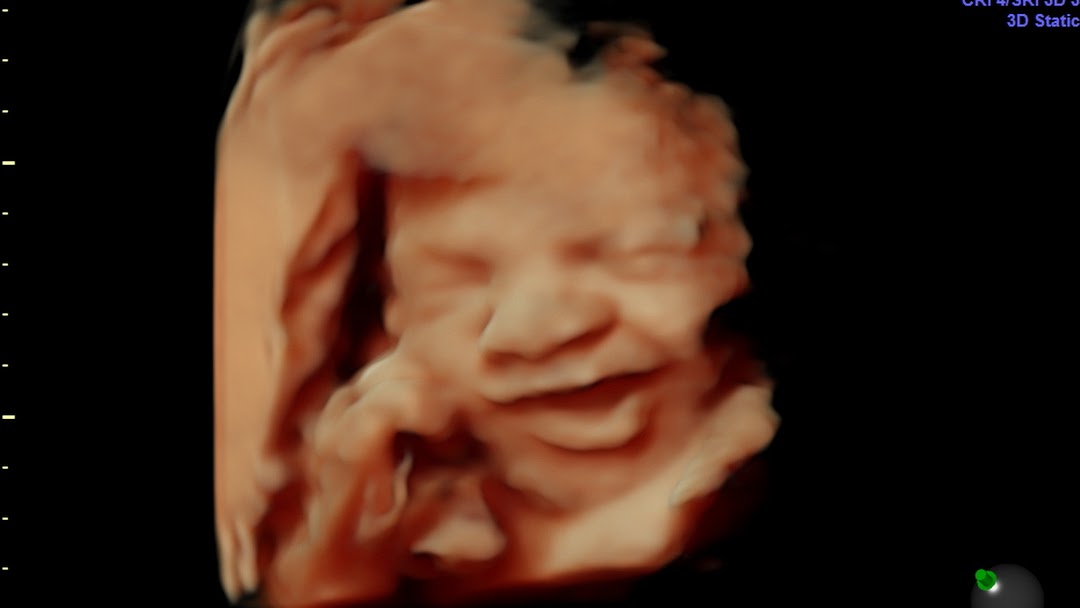

Your 4D Baby LLC it is an organization that is opening its doors in Miami Florida USA after 20 years of doing business in. A 4D ultrasound scan shows the live video of your baby and you may be able to watch them smiling or yawning inside the womb. Book 3d4d scan for 89.

An ultrasound image of a baby inside mom is an unbelievable breakthrough in modern medicine. They Specialize in 4D Ultrasound 3D Ultrasound Photography and. Book your 3d baby ultrasound in Miami now.